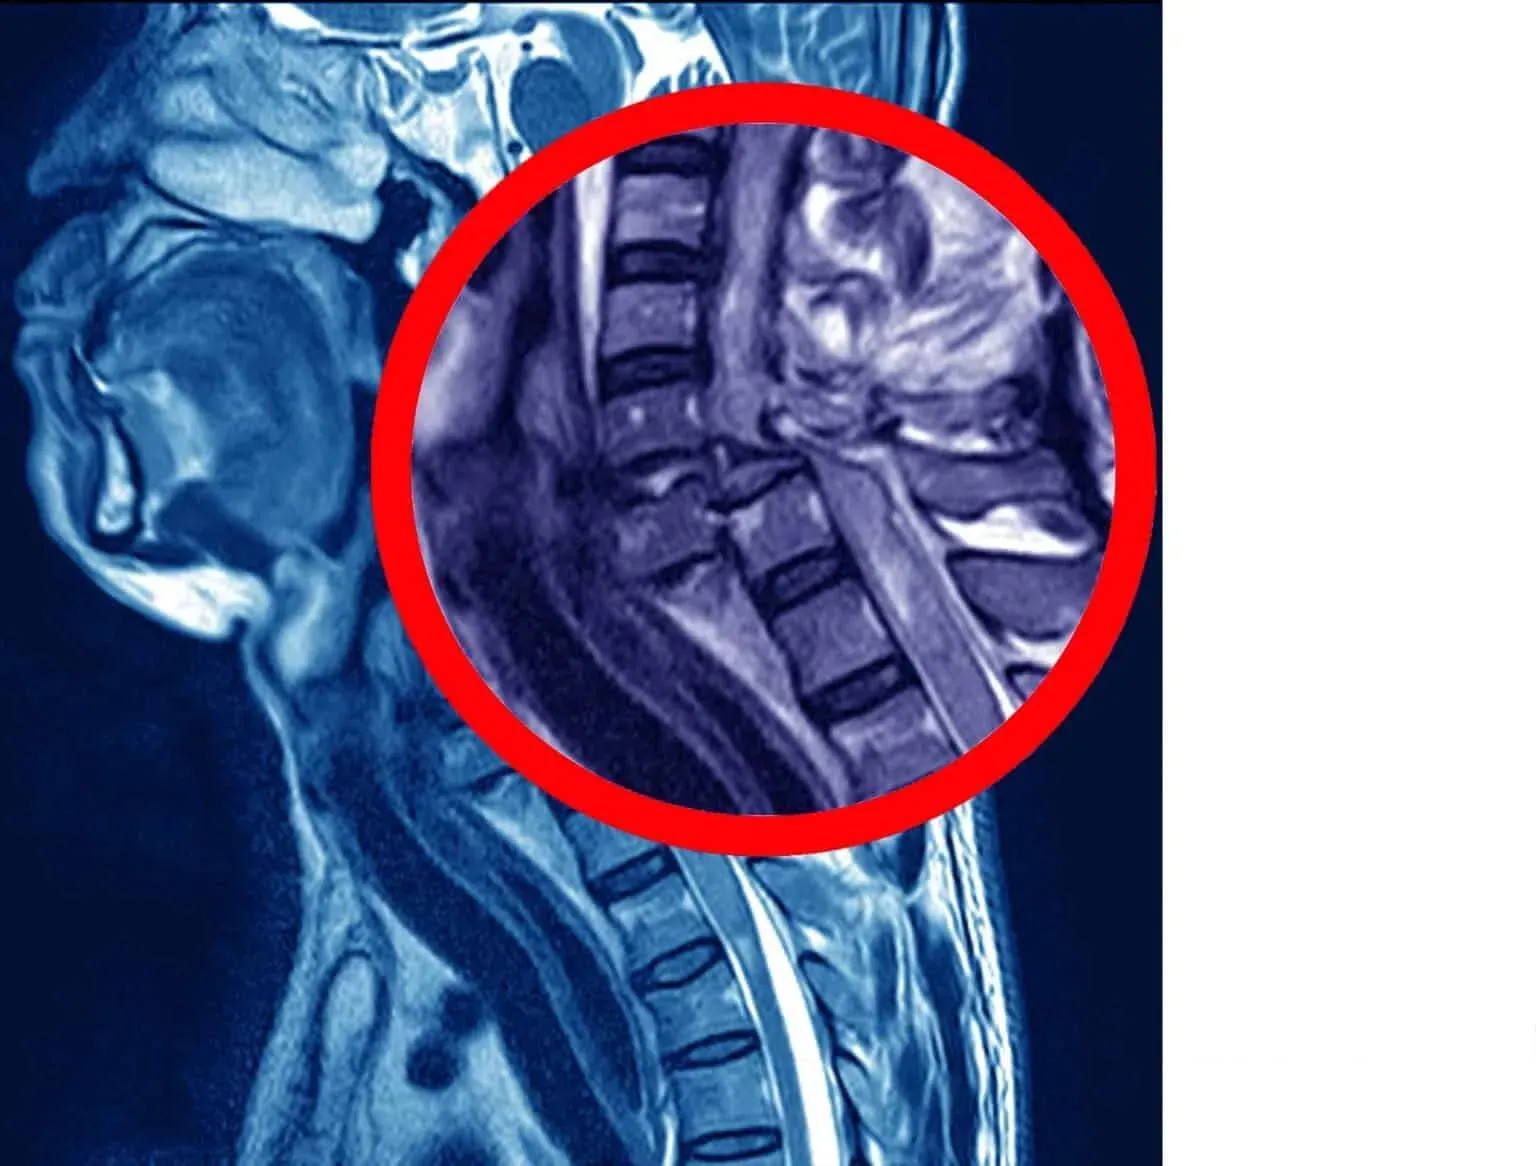

Spinal cord injury

Spinal cord injuries occur when damage to the spinal cord and surrounding tissues disrupts signals from the brain to other body parts. These injuries often result in paralysis or loss of sensation below where they occurred.